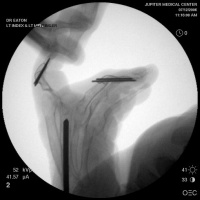

Below are xrays after the first set of reconstructions.

Her greatest desire was pinch reconstruction. This was approached in two stages: wrist fusion, implant removal and fusion of the index and middle PIP joints, followed by index and middle MCP arthroplasties. There are several alternative approaches, including index MCP fusion and revision PIP arthroplasties.